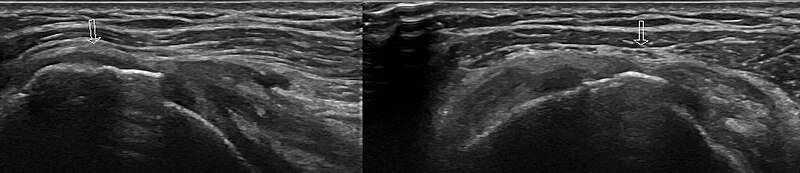

2. 초음파 :

초음파는 X-ray에서 관찰할 수 없는 연부조직들인 인대, 근육, 관절 내 염증 물질 등을 관찰할 수 있는 검사입니다. MRI에 비해서 저렴한 비용으로 검사할 수 있으며, 정적인 자세로 오랫동안 누워있어야 이미지를 얻을 수 있는 MRI와 다르게, 환자의 신체를 이리저리 움직이면서 다이나믹하게 여러부위를 실시간으로 관찰할 수 있는 장점이 있습니다. 다만 초음파 기기의 특성상 술자의 숙련도에 따라 얻을 수 있는 이미지의 편차 및 진단률의 차이가 있을 수 있습니다.

초음파는 파열된 회전근개 건조직을 직접적으로 이미지화 시킬 수 있으며, 염증이 심한 경우 동시에 주사치료를 시행할 수 있는 장점이 있어, 널리 사용되는 검사입니다.